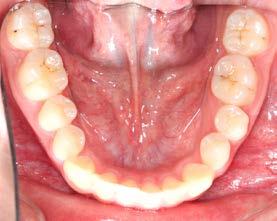

Las fotografías intraorales muestran las relaciones molares clase II y las relaciones caninas clase II bilaterales (Figura 3 y 4), espaciamiento anterosuperior, un overjet y overbite aumentado (Figura 5). La forma de los arcos es cuadrada, superior e inferior, con el apiñamiento moderado inferior y los espacios en superior.

Se observa dentición permanente, 28 dientes erupcionados, el canino

superior derecho y el canino superior izquierdo se encuentran en una posición ectópica, líneas medias dentales no se pueden determinar por mordida cruzada, forma de arco superior e inferior elipsoidal, clase I

molar bilateral y clase canina no se puede determinar por la posición de los mismos. Presenta crecimiento horizontal con retroinclinación de incisivos superiores (Figura 2).